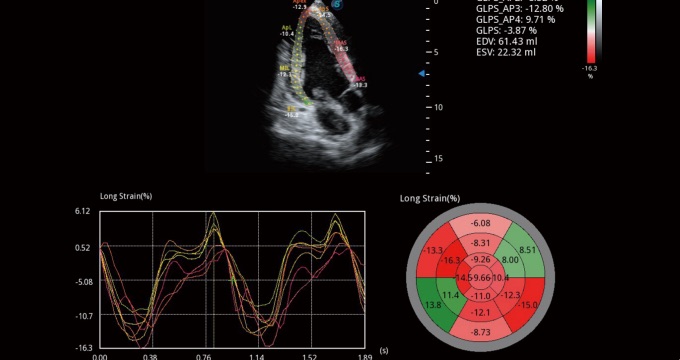

通過(guò)心肌識(shí)別技術(shù)和二維斑點(diǎn)追蹤技術(shù)相結(jié)合,計(jì)算心肌各節(jié)段的應(yīng)變應(yīng)變率、速度、位移并以曲線圖顯示,實(shí)現(xiàn)整體或者局部心肌定量分析。同時(shí)可呈現(xiàn)牛眼圖直觀和準(zhǔn)確診斷心肌的運(yùn)動(dòng)情況。